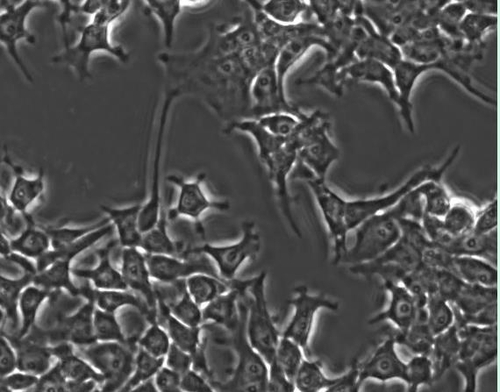

챗GPT가 위키피디아 자료, 책 등을 분석하고 학습해 콘텐츠를 생성하는 것처럼 프로플루언트의 생성형 AI 기술은 과학자들이 이미 인간 DNA를 편집하는 데 사용하는 아미노산과 핵산의 염기서열을 포함해 엄청난 양의 생물학적 데이터를 분석해 새로운 유전자 편집기를 만드는 것이다.

이를 위해 프로플루언트의 AI 모델은 2020년 노벨상을 받은 유전자 가위 기술 '크리스퍼'(CRISPR)도 학습하며, 더 정밀하고 빠르게 유전자 편집이 가능하게 하는 것이 목표다.

프로플루언트는 인간 DNA를 편집하기 위해 AI 생성 유전자 편집기 중 하나를 사용했으며 '오픈크리스퍼-1'으로 불리는 이 편집기를 오픈소스로 공개했다고 밝혔다.이에 따라 개인이나 연구기관, 기업이 이 편집기를 무료로 실험할 수 있다. 다만 이 편집기에 사용된 AI 기술 자체는 공개되지 않았다.